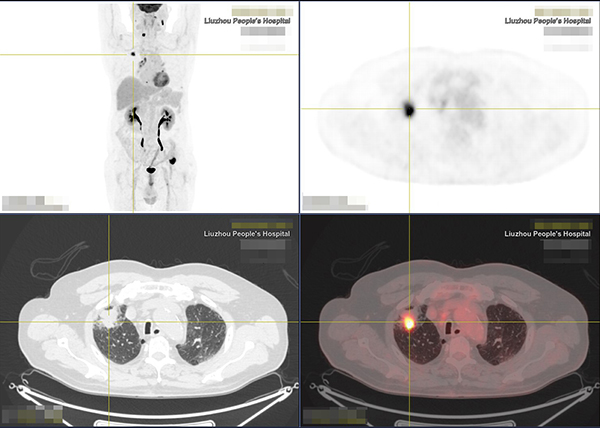

日前,66岁的文老伯因右侧头部有肿物10多天到我院就诊,头颅CT、MR检查及手术病理提示转移性皮质腺癌。那么,原发灶是什么,有没有其他远处转移,怎样的治疗方案更好?文老伯和家人非常茫然。

就在这时,医生介绍了一个评价分期的利器:PET/CT。通过PET/CT全身扫描成像,结果显示文老伯右肺上叶周围型肺癌,双侧颈部、纵隔及肺门多发淋巴结转移,第6颈椎椎体、第8胸椎右侧横突、左侧第8后肋、左侧髂骨多发骨转移。了解全身情况后,医生运用PET/CT的检查结果指导穿刺活检,精准选择最佳活检部位,提高活检准确率,穿刺结果显示肠型腺癌,低分化区30%,高分化区70%,为临床医生提供了全面精细的疾病诊治依据。

“早期肿瘤未发生解剖结构变化,传统的CT、MR检查均难以发现病变。但肿瘤细胞代谢活跃,PET通过对人体注射18F标记的脱氧葡糖,使病变区域出现异常“浓聚”,图像上表现为突出‘光点’,结合CT解剖成像,就能较早发现隐藏的肿瘤,精准判断肿瘤的良恶性,堪称探测肿瘤的雷达,可真正实现肿瘤的‘早发现、早诊断、早治疗’。” 柳州市人民医院放射科副主任邓奎品说,“PET/CT在肿瘤的早期定位、定性、分期、复发监测、靶区勾画、肿瘤疗效监测等方面具有重大意义,能为临床诊断提供更高效、更全面、更精准的影像学支持,为患者提供高科技、高品质诊疗服务。”